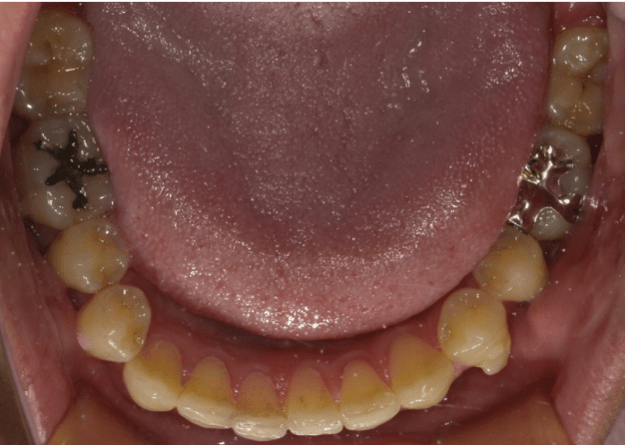

八重歯(重度叢生)

BEFORE

AFTER

担当医コメント

重度の叢生だが、患者の希望により非抜歯での治療を検討した。補綴が多いため補綴に対してのIPRでスペースを確保し、上顎大臼歯の遠心移動を組み合わせ治療することにした。上顎犬歯の歯肉退縮は患者の希望によりこのままで進める事にした。

治療の概要

年齢/性別

40歳 女性

主訴

噛み合わせ八重歯が気になる。上顎の歯が内側に入っているのが気になる

リスク

歯肉退縮が起こる可能性がある。

歯肉退縮を起こしている部位がより進行する可能性がある。

費用

85万円(矯正費用)

期間

2 6 ヶ月